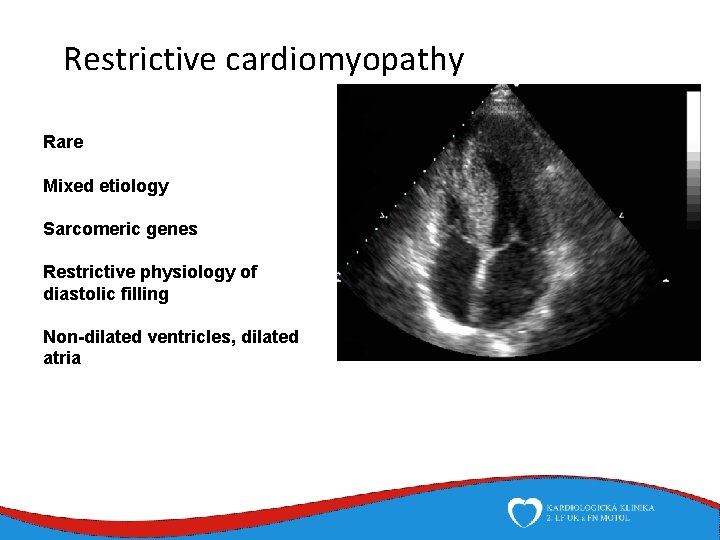

Restrictive cardiomyopathy Rare Mixed etiology Sarcomeric genes Restrictive physiology of diastolic filling Non-dilated ventricles, dilated atria